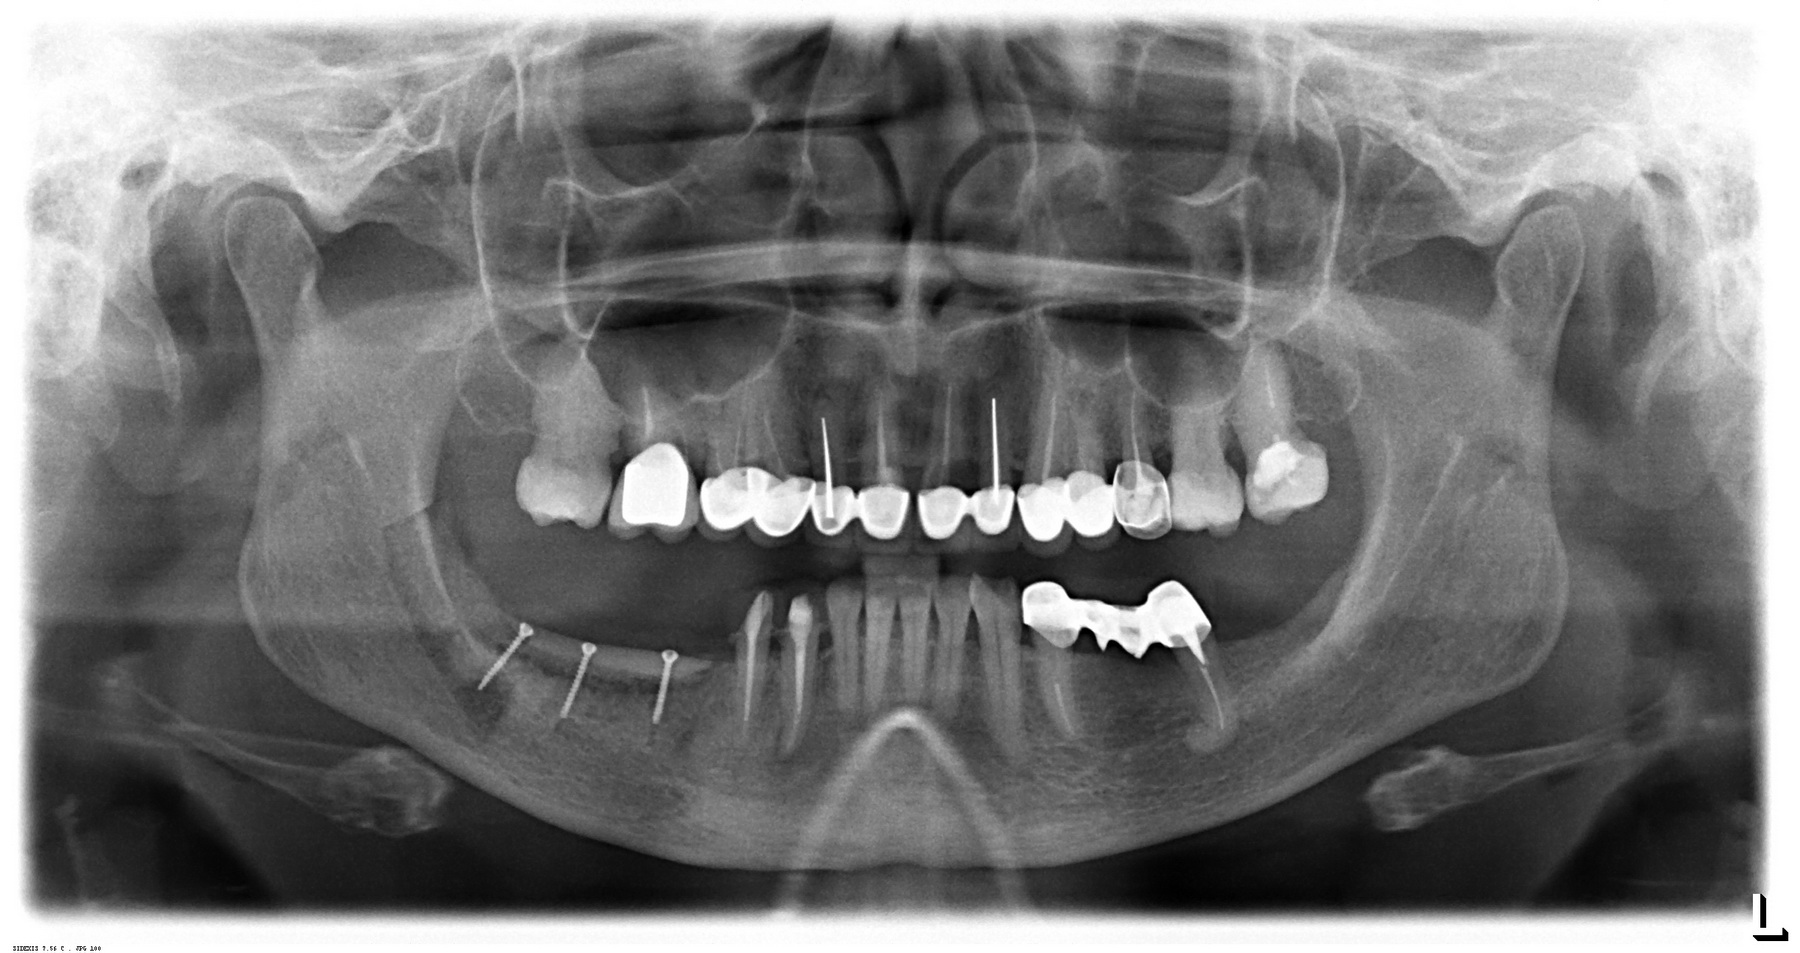

Через год после травмы, девушка обратилась в нашу клинику для восстановления отсутствующего зуба. К тому моменту у нее уже был временный съемный протез, изготовленный в вышеозначенном стоматологическом кабинете, ну и, вот какая клиническая картина:

Хочу спросить вас, уважаемые друзья, можно ли в таком состоянии и при таких объемах альвеолярного гребня поставить имплантат в область отсутствующего зуба? Безусловно, можно. Для этого нужно просто взять имплантат потоньше и поставить его подальше, в сторону неба — и он нормально интегрируется.

На фотографиях хорошо видны оставшиеся после удаления объемы костной ткани. Давайте рассмотрим плюсы и минусы текущей клинической ситуации, применительно к нашему плану:

Фактически, альвеолярный гребень атрофировался по толщине примерно наполовину — это минус.

Зато с высотой все в порядке — это плюс